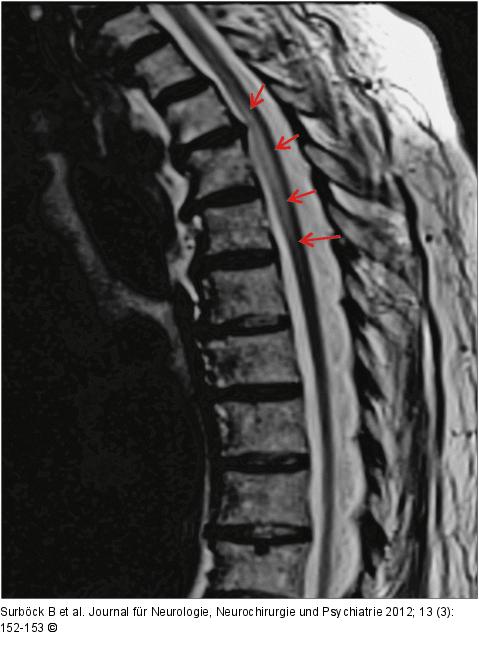

Abbildung 3: Arteria-spinalis-anterior-Syndrom

Signalalteration des Myelons auf Höhe Th2–Th4. |